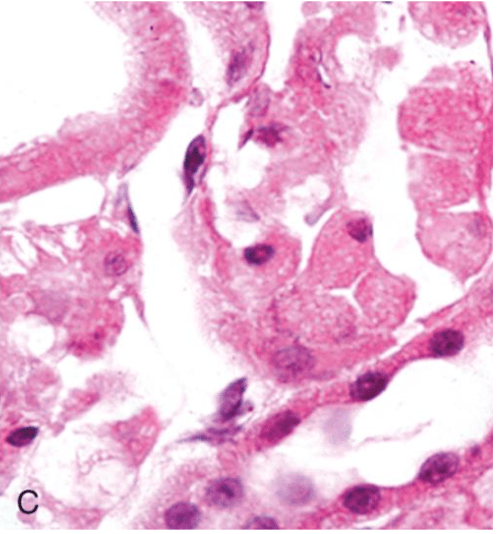

A normal Kindey Tubule

C Abnormal Kidney tubules

This shows what kind of cellular injury

Necrosis